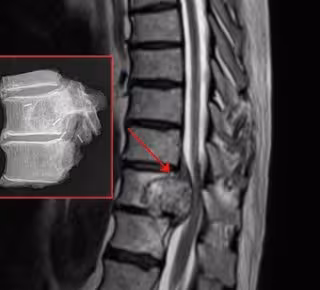

Cirujanos del Hospital Vithas Nisa 9 de Octubre de Valencia han realizado con éxito una resección en bloque de un cordoma que afectaba a tres vértebras, a través de una vía posterior única de acceso para la resección y reconstrucción de la columna.

Recientemente, el equipo que dirige el doctor Antonio Martín Benlloch ha intervenido con éxito en el Hospital Vithas Nisa 9 de Octubre a un paciente con un cordoma en la columna torácica, que en su evolución (afectaba a una vértebra y a las inmediatamente superior e inferior) ponía en riesgo la movilidad del paciente y que estaba produciendo una compresión de la médula espinal.

"Este tipo de lesiones obliga a extraer el tumor sin abrirlo, liberándolo por zonas no contaminadas, es decir, de una sola pieza (en bloque), con esta técnica el acto quirúrgico propiamente dicho incrementa las posibilidades de curación y evita el número de recidivas (reaparición del tumor)", ha comentado Martín Benlloch.

El paciente intervenido se trasladó a Valencia desde otra comunidad autónoma ante la imposibilidad de ser tratado en su ciudad de origen. "La lesión había crecido hasta ocupar la práctica totalidad del espacio epidural y estaba comprometiendo la médula; afectaba de lleno a una vértebra y a las adyacentes".